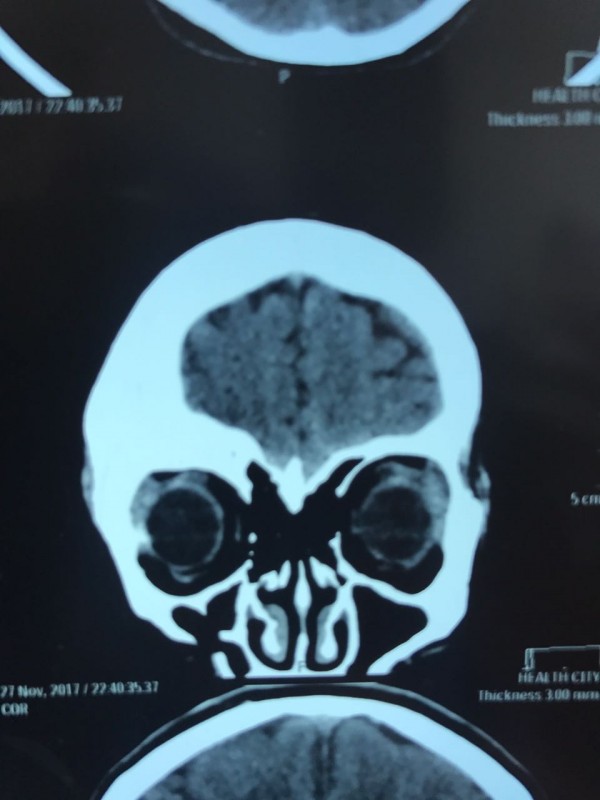

"Компьютерная томография показала, что костная опухоль поражала лобную кость и "крышу" орбиты глаза, которая, в свою очередь, сдавливала глазное яблоко. Чтобы убрать опухоль, потребовалось немало времени. Наша задача была сохранить глазное яблоко, зрительный нерв и сосуды. Если неправильно провести операцию и неправильно закрыть дефект, то в последующем это может привести к эстетической неполноте и асимметрии лица. Уникальность еще и в том, что в операции применялась 3D-стереолитография, которая делается только в Алматы", - рассказал он.

Снимок сделан до операции. Фото предоставлено Константином Ли